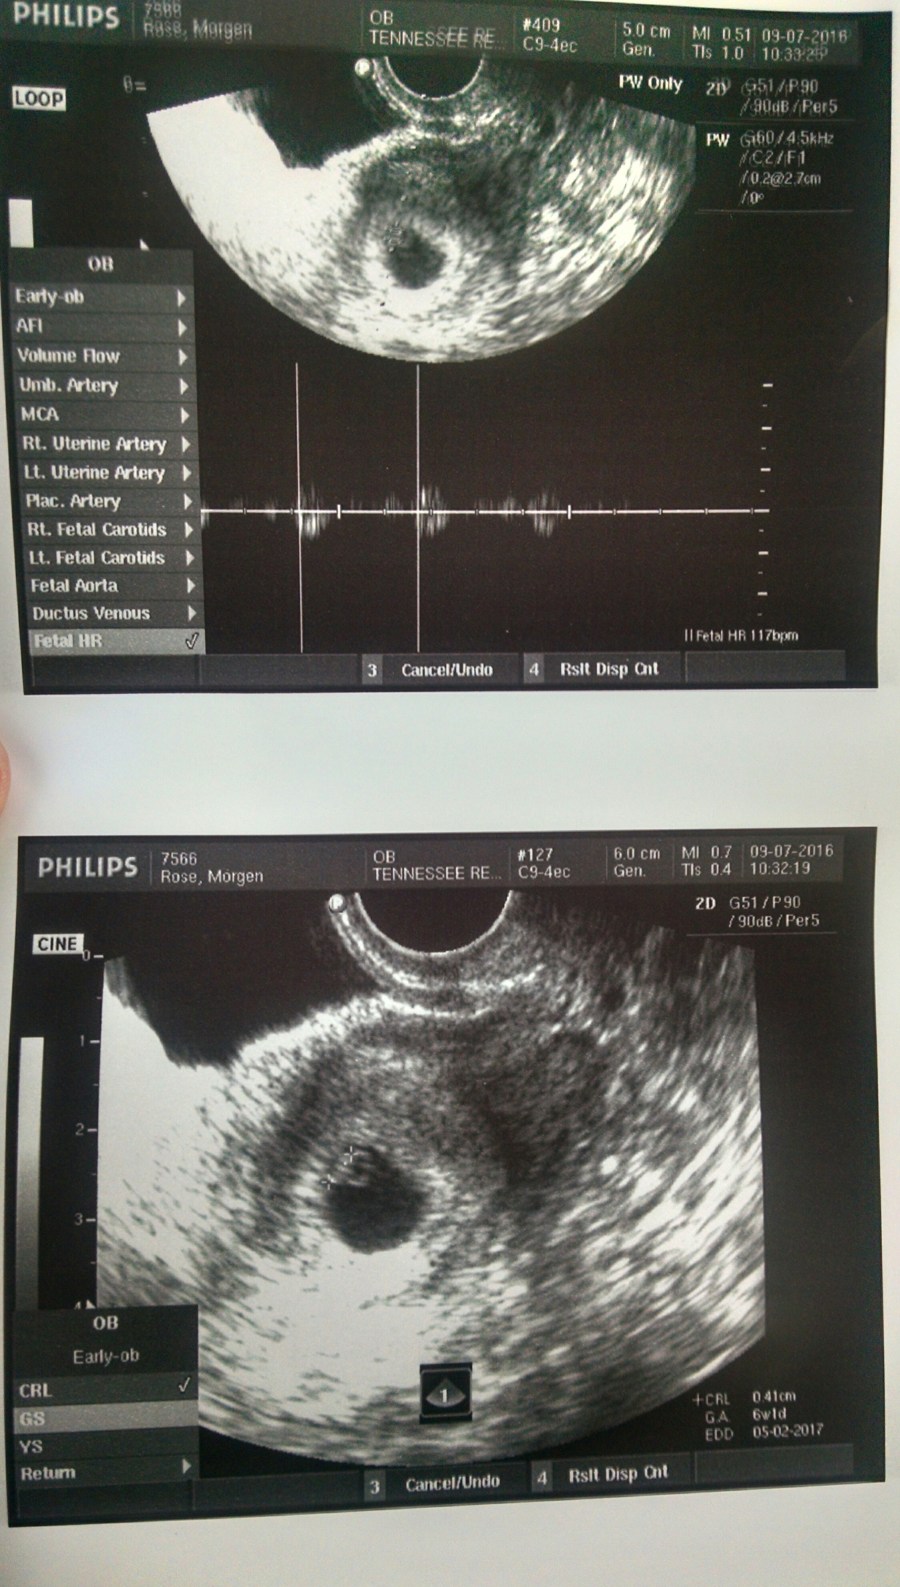

So she did the (transvaginal) ultrasound and lo and behold – there is a blob. And that blob measures exactly right. And that blob has a heartbeat. And I heard the heartbeat and I said “that’s weird.” Because that’s what all normal mothers do, right? They don’t burst into happy tears, they just cock their head to the side and say “that’s weird.”

Theoretically, I’ll be due 05/02/2017 and am currently 6 weeks along. After my 8 week scan, I’ll head over to the regular OB and bid farewell to TRM and Dr. Scotchie – which is good news, but a little sad. They got me this far and they’ve been great.

So, here you go, friends – here is the first photo of this new little person (it’s the blob).